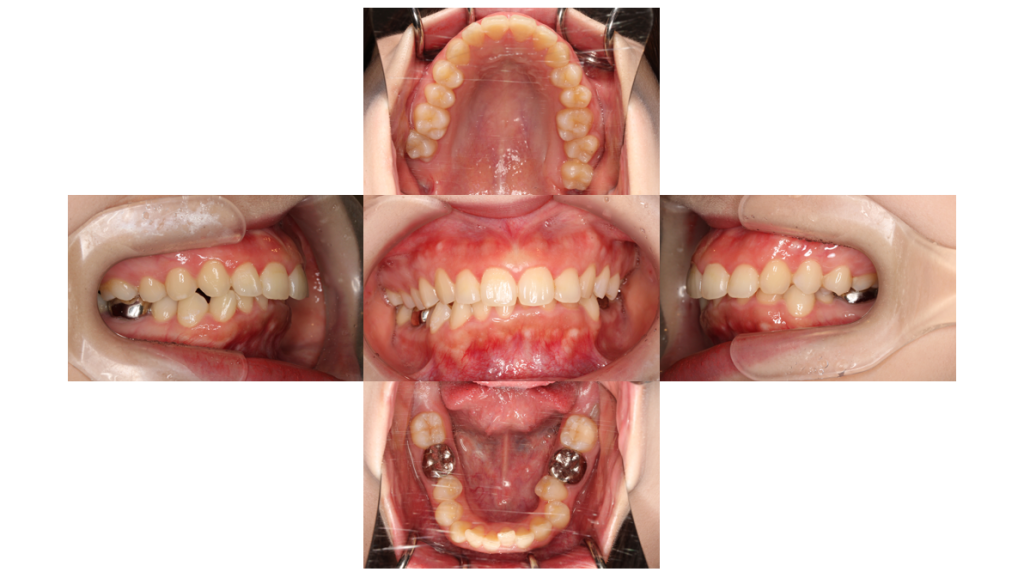

約16ヶ月経過

上顎前突・裏側矯正の症例上下とも抜歯窩を閉じるためにゴムで引っ張っていきます